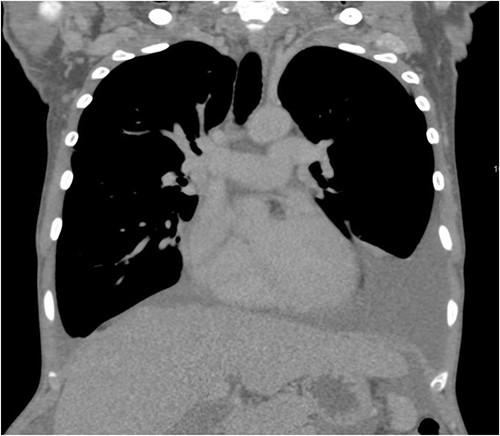

A 40-year-old Saudi, nulliparous woman, medically free with a history of leiomyoma (uterine fibroid) underwent myomectomy. She was referred to our center as a case of large abdominopelvic mass, tense ascites and pleural effusion. The patient complained of the shortness of breath, palpitation, marked abdominal discomfort and bloating as well as back pain. She reported that she first noticed the bloating 3 months prior to the visit. However, she was unable to come because of COVID-19 pandemic situation. She is a housewife; never smoked tobacco or drank alcohol, and had no history of recent travel to endemic or pandemic areas. On further investigations, a serum CA-125 was found to be elevated 492.6 U/mL (normal < 35 U/mL), whereas the concentration of other tumor markers LDH, CEA, CA19-9 and ALP was within normal ranges. Abdominal CT scan revealed a significant interval increase in the size of ascites, which caused a huge abdominal distention along with severe mass effects on the abdominopelvic organs, which have been displaced posteriorly as shown in Fig. 1. In addition, it revealed a large exophytic uterine fibroid measuring 15 × 20 × 17.5 cm. A therapeutic paracentesis was done with the removal of 50.750 ml of ascitic fluid. Figure 2 shows how pleural effusion is markedly significant. A total abdominal hysterectomy, with bilateral salpingo-oophorectomy and omentectomy, was performed. Intraoperative finding revealed a very large mass, which originated from uterine fundus. The pleural effusion and ascites disappeared entirely after the excision of abdominopelvic mass. She recovered completely and went through an uneventful postoperative period. On pathology of surgical specimens, a giant uterine leiomyoma with degenerative changes, pleural and ascitic fluids was yielded negative for malignancy and diagnosed as a benign mesothelial proliferation, whereas H&E stain of the omentum excision surprisingly confirmed multiple, large and irregular disorganized veins (thin-walled blood vessels) and arteries (thick-walled blood vessels), some with organized thrombi consistent with omental AVM as shown in Figs 3 and 4. Provisional diagnosis of pseudo-Meigs’ syndrome with omental AVM was considered.